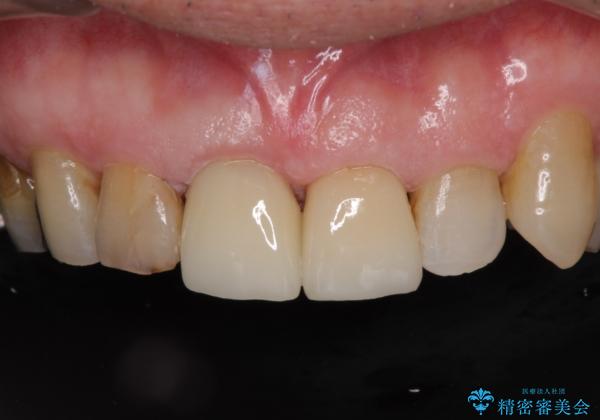

差し歯(被せ物)のやりかえ 上の前歯で印象が明るく

- 前歯がぐらつくことを主訴にご来院された患者様です。ご本人は抜歯と考えており、インプラント以外の治療をご希望でした。しかしながらぐらついていた原因は、古い差し歯が取れかけていたことでした。

遠方から通院されること、仕事上短期間で治療したいとのことを考慮して、残っている歯はかなり小さいものの、保存すべきと判断して当日処置から行いました。

西日本から新幹線でご来院された患者様です。前歯は都内の医院でやりたいとのことで、はるばる通院してくださいました。通院回数が最小限になるよう工夫しました(1回あたりの時間は長くなります)。

残っている歯が小さいと、差し歯はぐらつきやすくなりますが、その形態によっては抜歯を回避できることがあります。